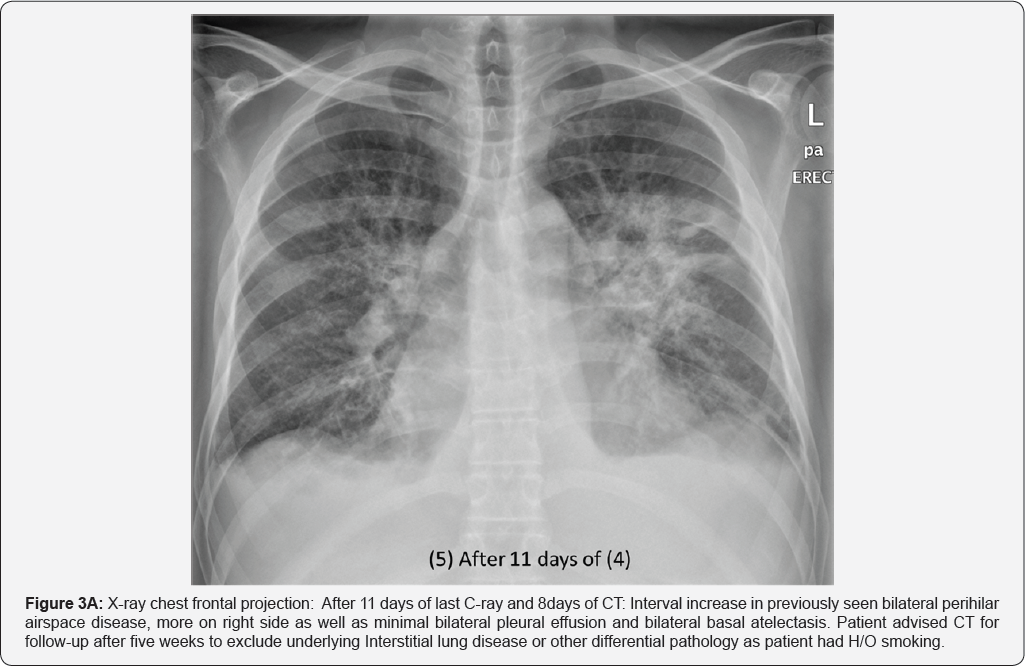

X-Rays and CT during his Hospital stay: (Figure 2A-2E)

Pleural effusion (RT>LT) multiple small mediastinal lymph nodes (arrow in image a & b), likely reactive. Bilateral perihilar airspace diffuse air space opacity and ground-glass attenuation with superimposed interlobular septal thickening and intralobular lines (LT> RT). Common differential of Crazy paving given as well as diagnosis of pulmonary edema (uncommon cause of crazy paving) given in view of history of CHF and improvement by treatment. Superimposed infection is likely in view of high inflammatory markers (Figures 3A & 3B).